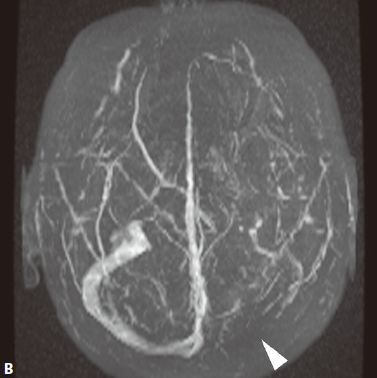

1. 脑静脉性血管瘤 极为少见。静脉性血管瘤是一种组织上完全由静脉成分构成的脑血管畸形,任何年龄均可见,病理特点为许多放射状排列的扩张髓静脉连接成一条或多条扩张的经皮质或室管膜下引流静脉,最后汇入静脉窦。常发生于 额叶及小脑,以第四脑室周围多见 ,常伴发其他血管畸形,最常见为海绵状血管瘤。

2. CT表现:平扫显示不清,周围无脑水肿,有时可见出血等改变,CTA典型表现为额叶或小脑许多细小髓静脉放射状汇入一条或几条引流静脉,最后汇入静脉窦,呈“水母头征”。

3. MRI表现:可因病灶大小及血流速度不同而在MRI上呈多种信号,T1WI、T2WI多呈流空信号,少数由于血流缓慢也可呈略高信号,FLAIR呈低信号。增强后髓静脉及引流静脉明显强化,典型者呈“水母头征”,引流静脉可走向脑表面而引流至静脉窦,或走向脑室引流至室管膜静脉。MRV可显示引流静脉及其引流情况,但不显示髓静脉,SWI序列对本病显示很敏感。病灶周围无脑水肿表现,有时可见出血。

4. 鉴别诊断:动静脉畸形:由供血动脉、畸形血管团、粗大引流静脉构成。海绵状血管瘤:多可见不同时期反复出血的产物,周围脑实质多有脑萎缩改变,MRI呈爆米花样改变为特征,周边见含铁血黄素环,增强后轻度或无去强化。